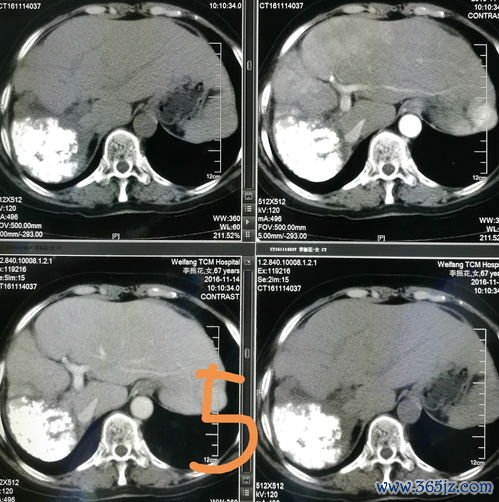

诊断上,对于有肝炎、肝硬化病史,突发腹痛、腹胀伴休克表现的患者,应首先考虑本病可能。急诊腹腔诊断性穿刺抽出不凝固血液是快速、重要的诊断依据,阳性率极高。腹部超声、CT(特别是增强CT)检查能迅速明确肝内占位性病变、破裂口位置及腹腔内出血量,为治疗决策提供关键信息。